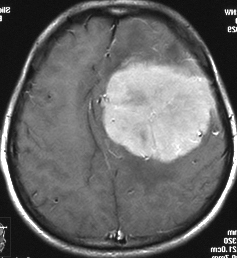

典型的な髄膜腫

この髄膜腫は中程度の大きさのものです。円蓋部髄膜種という最も多い最も手術の簡単なタイプです。麻痺や失語症やてんかんなどの症状はありません。とても美しくて若い女性の髄膜腫でしたが,子供に遺伝はしませんし,癌などと違ってタバコなどこれといった原因がなくて発生するものです。

MRIでの髄膜腫の見え方は撮影の仕方によっていろいろです。左からT1強調画像,T2強調画像,フレア画像といいます。腫瘍の横に小さく白い領域がありますが,これは脳の腫れた部分で脳浮腫といいます。髄膜腫があると周囲に脳浮腫が生じることがあります。

最も見やすいのが,ガドリニウム造影剤を注射して撮影するものです。一般的に髄膜腫は造影剤で白く映し出されます。この腫瘍は左脳側にあります。MRIの軸面という輪切りの写真では左右が逆になりますから注意してください。脳を下から見た図になっています。MRIはいろいろな方向から腫瘍を見ることができますが,右は冠状断という正面から見た図です。よく見ると腫瘍の上と下のはじっこに線状に糸を引いたように造影される部分があります。これをテールサイン(しっぽのサイン)といいます。腫瘍が硬膜に沿って延びている可能性があることを示しています。